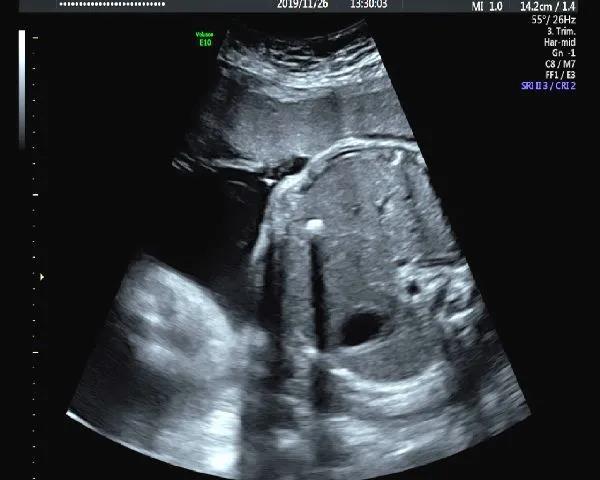

4.肾脏皮质回声增强

肾脏皮质回声增强往往是多囊肾、肾发育不良、一些综合征的表现(Meckel-Gruber综合征)、染色体异常等疾病的一种表现。当看到肾皮质强回声时,需要专业的产前诊断医生给您进一步建议,包括我们产前诊断羊水穿刺,甚至需要家族做泌尿系超声检查,协助一些遗传性疾病的诊断。

那是不是肾皮质强回声的胎儿都不能要了?当然不是,有一些正常肾脏发育中也存在这样变异,同时某些肾脏的问题预后也是比较好的,所以宝妈们不要轻易地放弃,也不要盲目的赌博。来产前诊断门诊,让专业的产前诊断医生给您专业的解释和评估。